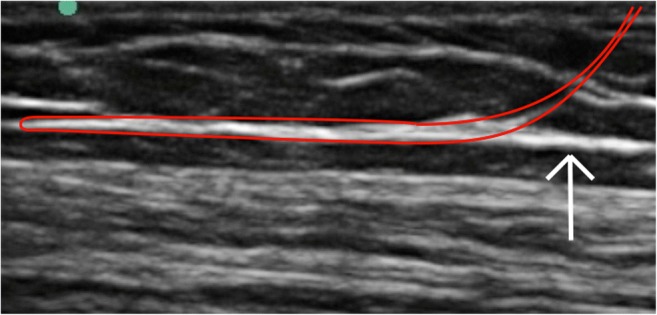

Fig. 6.

Ultrasound image demonstrating the intended location of the thread (red line), looped immediately superficial and deep to the fascial layer to be divided (white arrow)